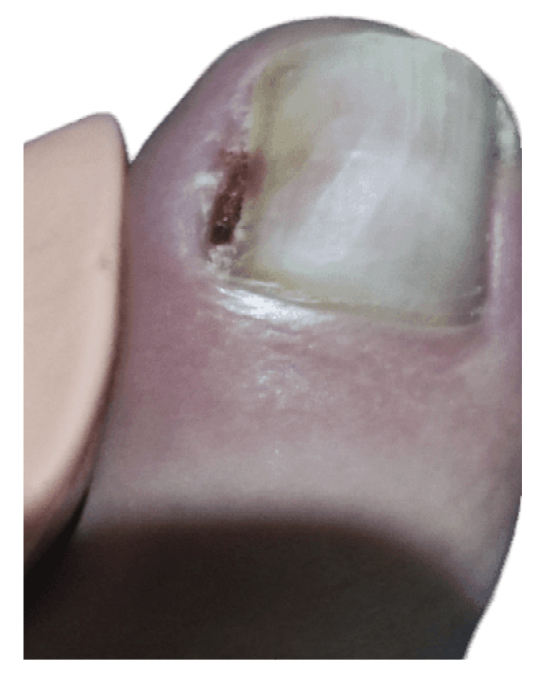

Within 3 weeks after the third intervention, the patient reported recurrence of the lesion and painful symptoms (Figure 7). The patient decided to attend the traumatology department (February 2023) where an MRI (T2FS and DPFATSAT) was requested. It showed an occupying mass in the lateral third of the first toe with well-defined borders and bone involvement (Figure 8) with the following report: “At the level of the distal phalanx of the 1st toe in the nail region, there appears to be a solution of skin continuity with a heterogeneous, a dense 15 mm x 14 mm collection in the lateral region of the parapharyngeal soft tissues, remodeling the bone and coming into contact with the flexor tendon, which could be consistent with a postoperative abscess/phlegmonous collection. Some bone edema in the distal phalanx is suspected, without completely ruling out incipient osteomyelitis. To be correlated with medical history and surgical protocol performed.”

Figure 7. 21th week. Recurrence of lesion after phenol-alcohol surgery.

Figure 8. Space ocuping mass with bone involvement. A: transverse plane; B: saggital plane.